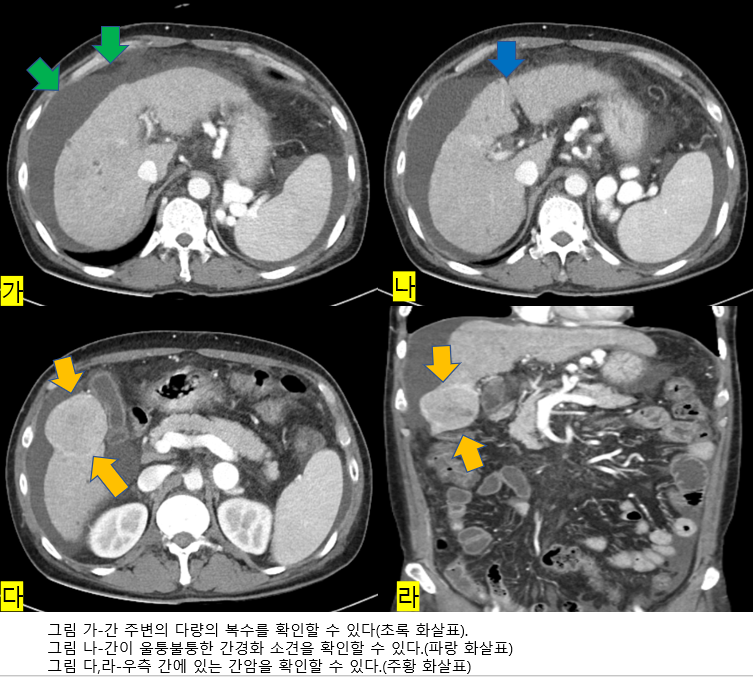

여름이 지나도 더위가 지속되어 반팔티셔츠를 입은 사람들이 거리를 활보하던 2022년 9월 중순, 발열을 주소로 50대 초반의 남자분이 응급실에 방문하였습니다. 환자분은 다리의 연조직염 (피부 균열이나 상처, 화상, 물집, 벌레물림, 수술 상처 등에 세균이 감염된 상태) 으로 인해 정형외과 입원 예정이었으나, 피검사에서 total bilirubin 이 6.03 mg/dL (참고치는 1.2 mg/dL 미만) 으로 상승되어 있고 황달이 심해 소화기내과에 의뢰되었습니다. 환자를 진찰하였을 때 양다리의 부종이 관찰되었고 복부 팽만이 심하였습니다. 정확한 평가를 위해 복부 CT 검사를 하였고, CT에서 복수와 간경화 그리고 우측 간에 약 5cm 크기의 간암이 의심되는 병변이 관찰되었습니다. (그림 1) 입원하여 검사 및 치료를 하기로 하였습니다. 복수를 빼기 위해 이뇨제를 투여하고, 알부민수치가 낮아 알부민도 처방하였고, 위내시경을 시행하여 식도의 정맥류여부를 확인하였습니다. 다행히 정맥류는 없었으나, 간암의 표지자인 AFP 이 12133.41 ng/mL (참고치는 8.78 ng/mL 미만) 으로 크게 상승되어 있었으며, 간 MR(자기공명영상) 검사에서도 간암의 소견이 명확하였습니다. 이 환자에게서 간암이 발생한 원인을 확인하기 위해 바이러스 검사를 하였고, 바이러스 검사에서 B형 간염 바이러스의 표면항원(HBsAg) 이라는 혈액검사가 양성이 나오고, 바이러스 DNA 역가 검사도 크게 상승되어 있었습니다. B형 간염에 의한 간암으로 확인이 되어 항바이러스제 투여를 시작하였습니다. 연조직염에 대해 정형외과와 협진하여 치료를 하고 간경화, 간암에 대한 보존적 치료를 열심히 하였고, 증상이 호전되어 퇴원하였습니다. 하지만 간암에 대한 근치적 치료를 하지 않으면 결국엔 사망까지 이를 수 있습니다. 간암에 대한 근치적 치료를 위해 이 환자에게서는 간이식이 필요하나, 간이식 공여자를 구하지 못한 상태로, 간성혼수가 반복적으로 생겨 입원치료를 반복하고 있습니다. 간성혼수란 간 기능이 많이 손상되어 각종 독성물질이 뇌 조직에 영향을 미쳐 신경전달의 이상이 초래됨으로써 의식, 행동 및 성격 변화, 신경 장애 등이 유발되는 것을 말합니다. 위의 경우처럼 B형 간염을 조기에 진단하고 치료하지 않으면 간경화, 간암이 발생하여 환자는 큰 고통을 겪게 되며, 간이식을 하지 못할 경우 생명이 위험해질 수도 있습니다.

그림 1 환자의 CT 사진